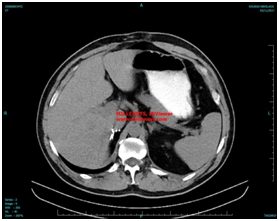

The findings where constinent of a large eggsize tumour, weight 95 gr, dimension of 8x6,5x1,8 cm, with smooth external surface. The epitheliods cells are in some locations wasllowed in dense stroma of inotic places. The immunochemistry revealed CK 27 +, Vim (+), Calretinin(=), Chromogranin (-), CK20(-), findings which represent mostly adenomatoid tumour of right adrenal gland (Figure 2).

Figure 2 The postsurgical findings can be shown in the next image.